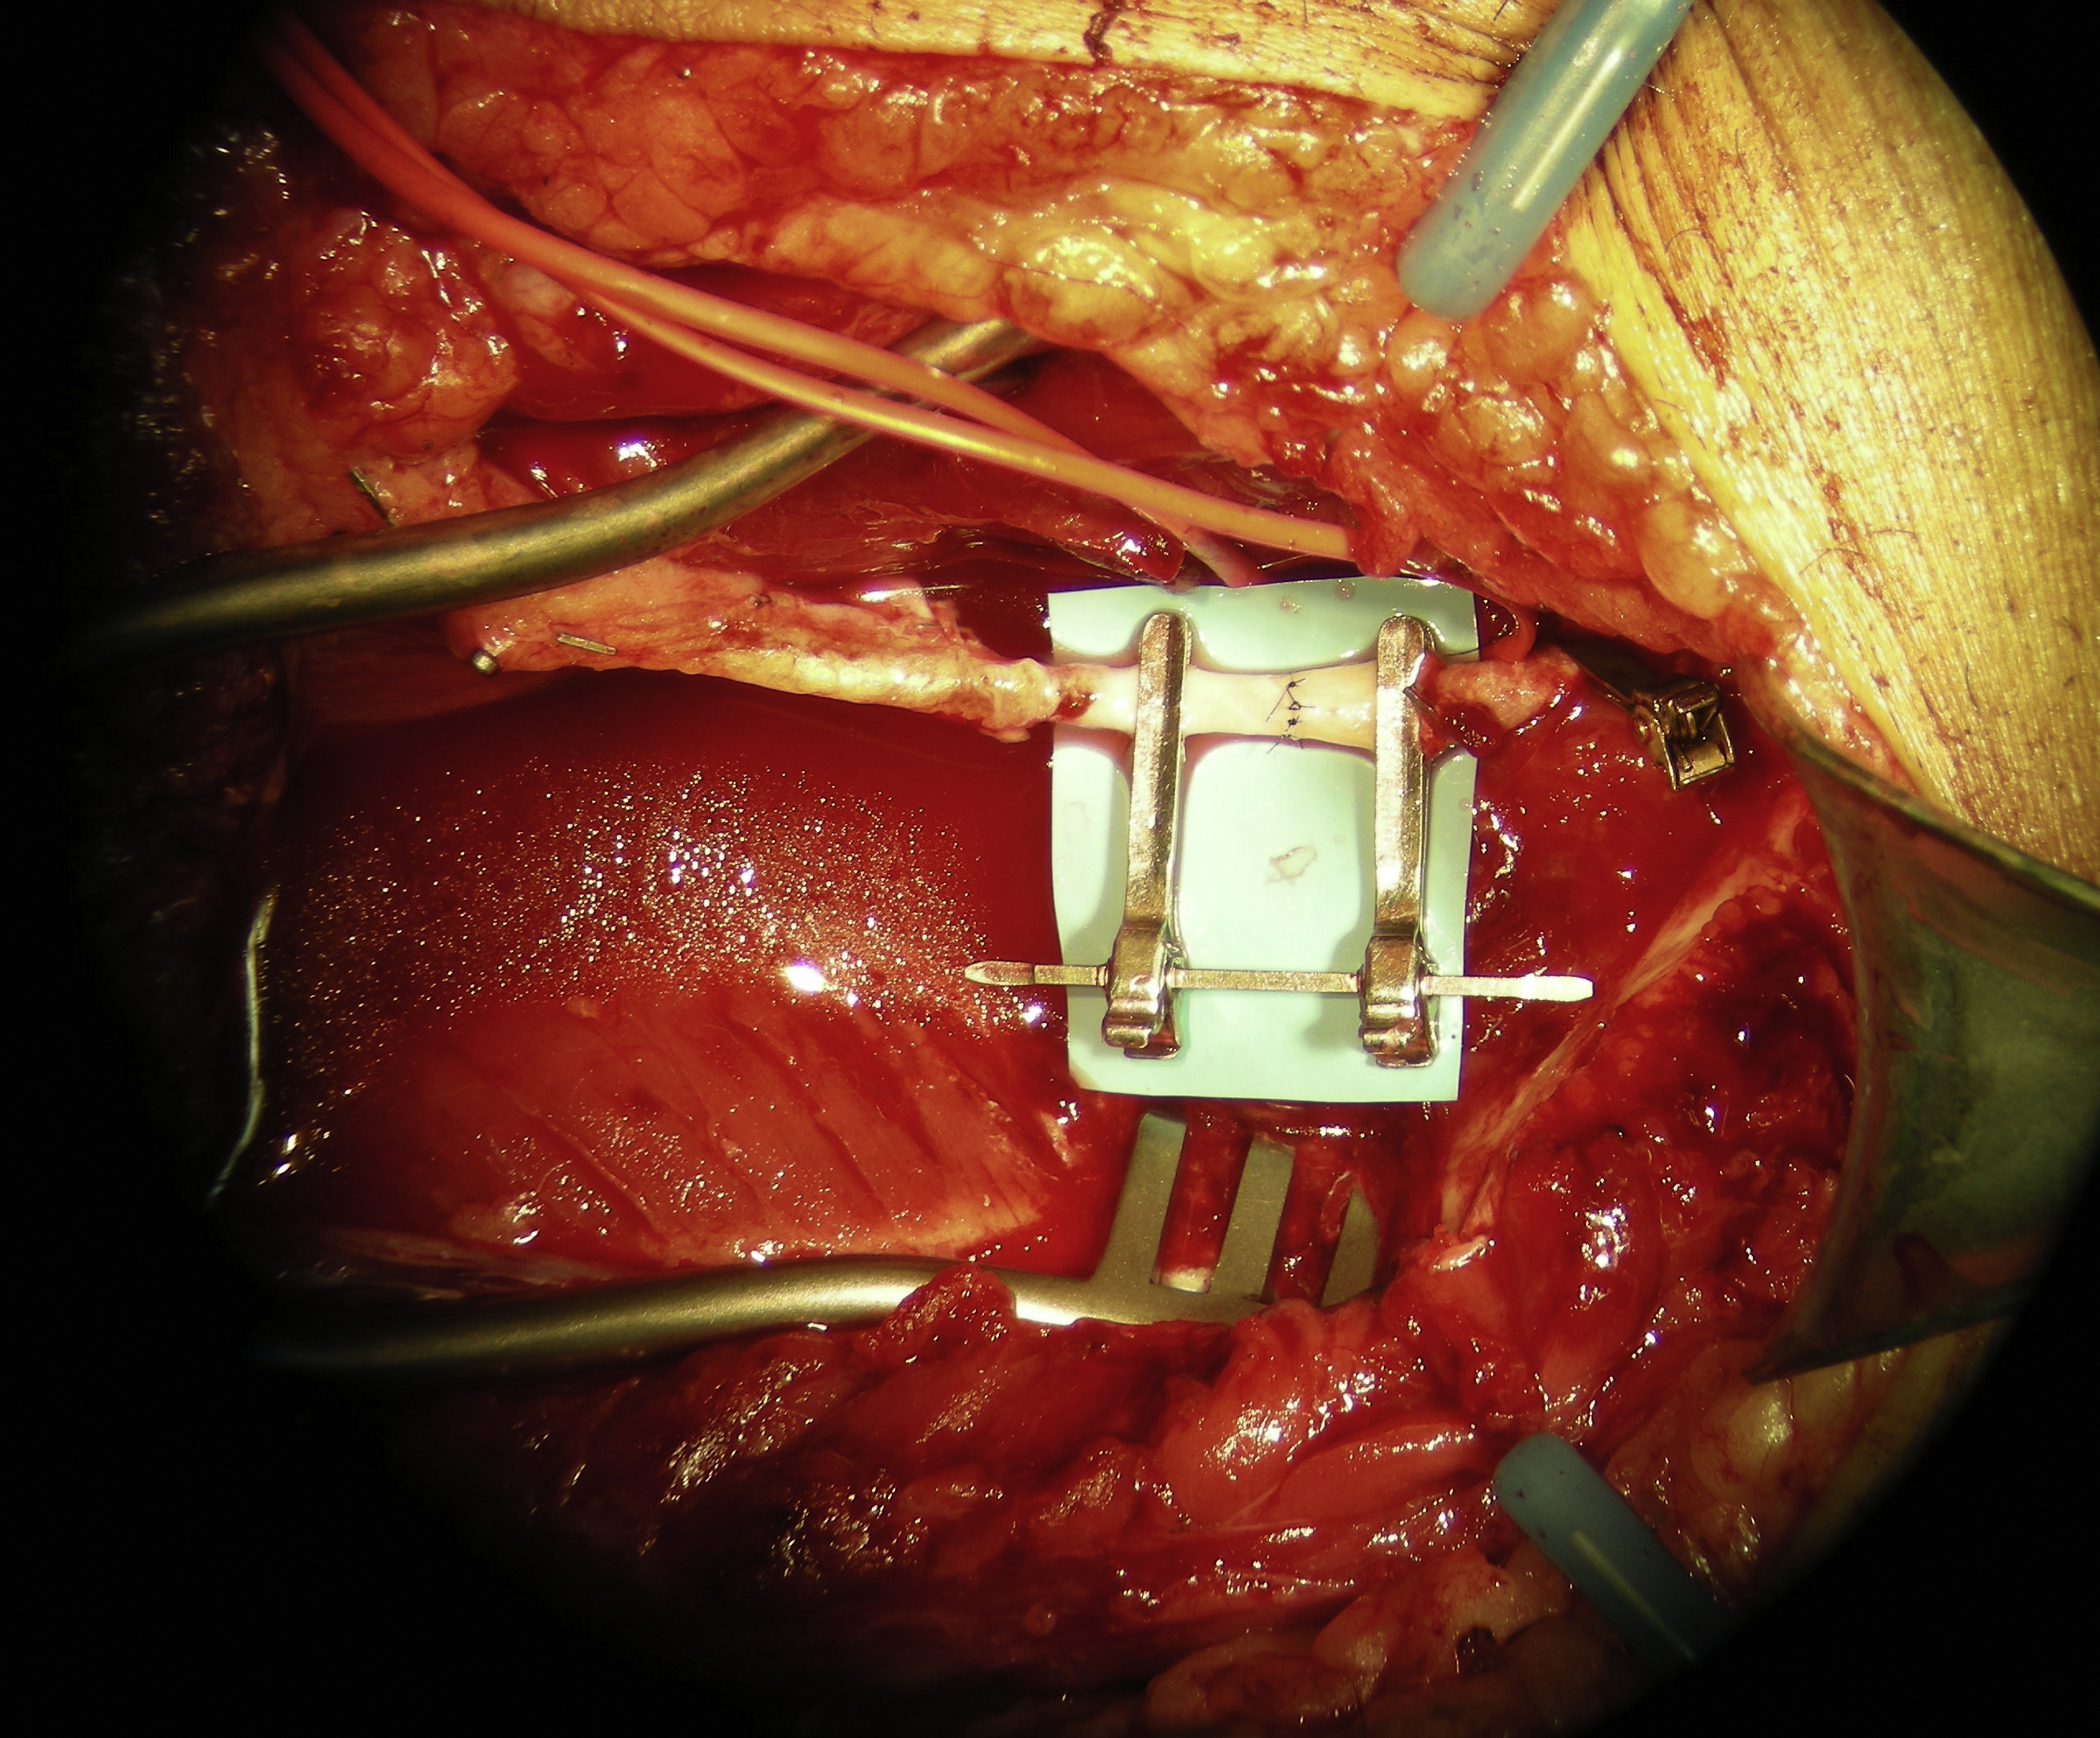

Before microvascular anastomosis, the surgeon should take time to set up the vessels. It is the author’s preference that a double-armed microvascular clamp is used to aid an end-to-end arterial microanastomosis ( Fig. 3 ). For an end-to-side arterial microanastomosis, an adequate size and shape of an arteriotomy over the recipient artery should be performed to ensure a successful end-to-side arterial microanastomosis ( Fig. 4 ). The author prefers to use an 8-0 nylon suture for routine arterial microanastomosis when the size of the pedicle artery is greater than 1.5 mm, resulting in fewer sutures needing to be placed to the anastomosis.